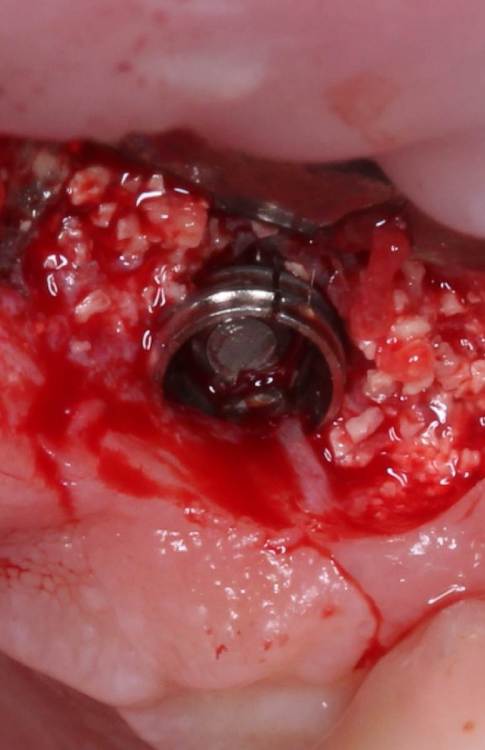

АнтонТЛТ Опубликовано 4 июня, 2021 Поделиться Опубликовано 4 июня, 2021 Жил да был имплантат 3.5мм, прижимался хорошо вместе с поджсаженной костью. Но в один момент ортопед со злобным техником решили его запротезтровать неоригинальным тибейсом в составе цирконевого моста. Имплантату это не понравилось и он решил, что ему пора на покой. И сделал себе харакири. А чтобы не сильно травмировать пациента, было решено удалить винт и имплантат. Затем сразу же поставить имплантат чуть короче и немного потолще. Время работы 50минут с учётом фотографий. 3 Ссылка на комментарий

АнтонТЛТ Опубликовано 4 июня, 2021 Автор Поделиться Опубликовано 4 июня, 2021 1 час назад, Irouil сказал: Винт, насколько я понимаю, удалялся реверсивным сверлом. А чем удалялся сам имплант? Fr-kit neobiotech 1 Ссылка на комментарий